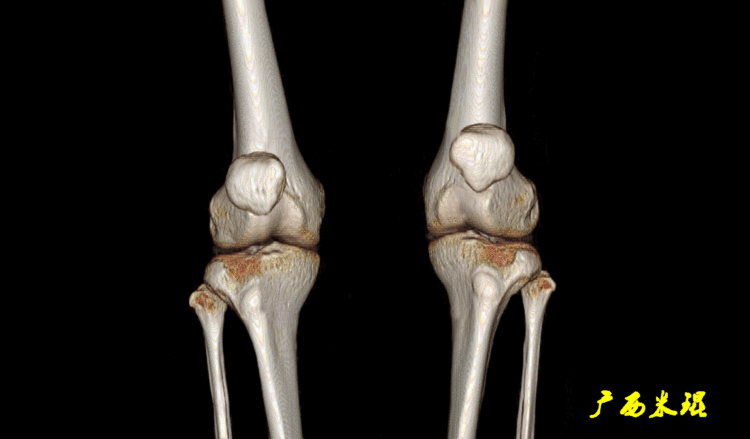

CT检查相对于DR检查,其主要优势在于其不仅不受体位影响,还可以动态观察膝关节伸屈活动中的髌股相对位置,能够提供髌骨不稳的准确信息,克服轴位X线片的不足,而且为了克服单层CT扫描中选点造成的测量误差,还可以使用图像叠加技术用于测量髌股关节排列关系,提高诊断率。